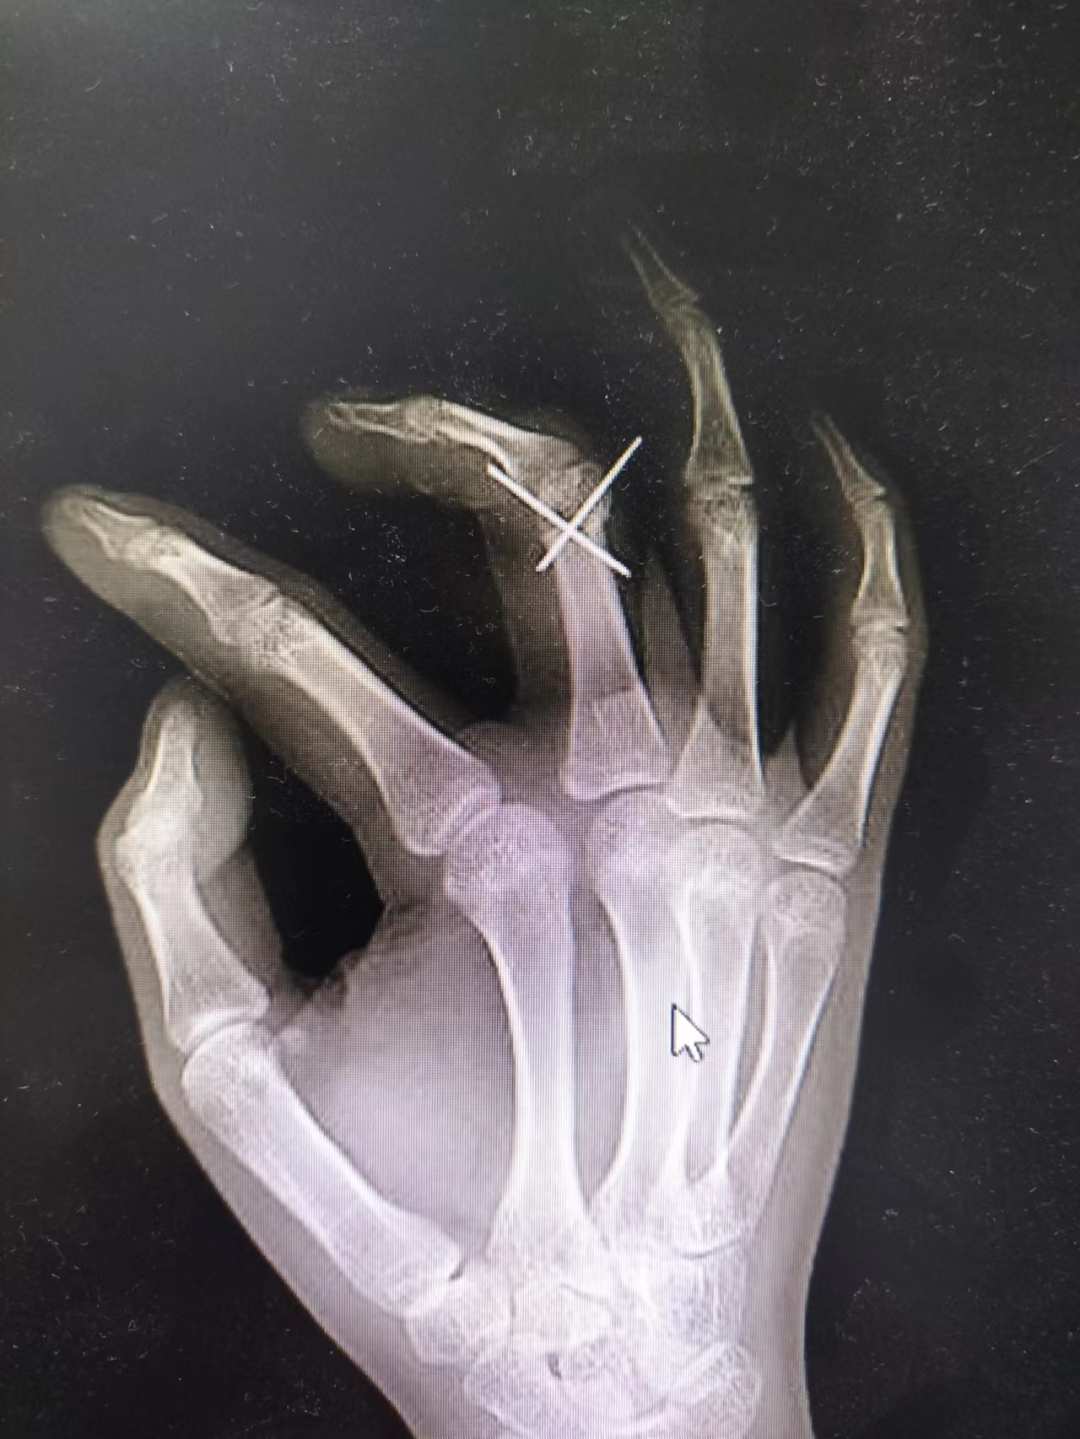

手足外科团队详细告知患者及家属诊疗方案,并征得同意后,迅速组成专家团队。经过细致周密的术前准备,手足外科团队历时1小时顺利为患者实施了3D打印技术截骨矫形手术治疗,患者术后复查X片手指功能恢复良好。